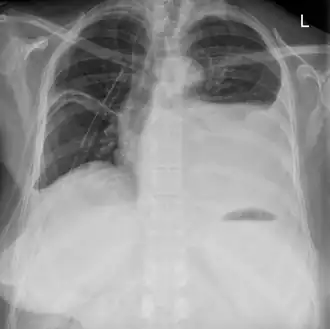

Een hydrothorax is een abnormale toestand waarbij er vocht in de pleurale ruimte gelekt is, met als gevolg dat de long kleiner geworden is.

De pleurale ruimte is de ruimte tussen het binnenste (viscerale) en het buitenste (pariƫtale) longvlies (pleura). Normaal is deze ruimte leeg (een virtuele ruimte) op een dun filmpje pleuravocht tussen de longvliezen na. Normaal heerst er ook een onderdruk ten opzichte van de atmosferische druk. Hierdoor blijft de long deze ruimte maximaal vullen. De long op zich heeft immers de neiging om samen te trekken door haar elasticiteit.